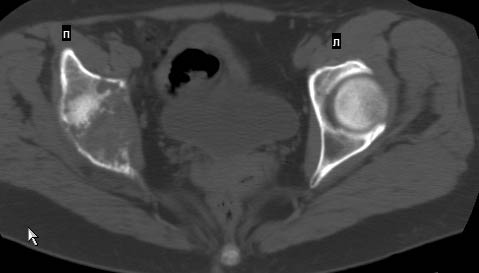

Сохранная по соматической патологии женщина ,47 лет. В 1996 г. установлен диагноз- cr левой молочной железы Т2N1Mo (2б)- проведено комплексное лечение- мастэктомия по Холстеду, ДГТ, 5 курсов ПХТ по схеме CMF. Сейчас менопауза уже 6-7 лет. В декабре 2004 года на профилактической остеосцинтиграфии с Тс99- выявлен единичный очаг повышенной фиксации препарата в зоне правой седалищной кости, рекомендована Рентгенография костей таза, выполнена- без патологии. УЗИ брюшной полости и Р-графия легких от конца апреля 2005 года - без патологии. Приблизительно 3 месяца назад появился болевой синдром в правом т/бедренном суставе с тенденцией к усилению. На рентгенограмме таза от мая 2005 года по заключению Рентгенолога очагов остеодеструкции не выявлено. Сегодня сделал ей Кт костей таза (картинки в приложении)- очаг деструкции в правой седалищной кости в зоне крыши вертлужной впадины.Что можно и нужно сделать? Жду советов, мнений, предложений по дальнейшей тактике ведения больной. С уважением, Корнев А.В.

Сам не имея опыта лечения подобных больных, сегодня показал представленные снимки специалисту по костной онкологии (Dr. Kurt Merkel), партнеру по работе.

Его мнение: в данный момент облучение не более 2000-3000 рад, через три недели операция по удалению процесса "кюретажным методом" затем ввести несколько спиц с резбой на конце в различных направлениях (создавая как бы внутренную арматуру) метод Harrington?, потом полость залить цементом, вариант костной пластики тоже не исключает.